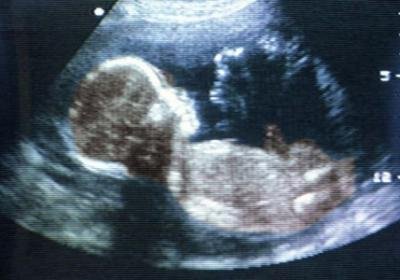

Роды – это физиологический процесс, во время которого уже приспособленный для самостоятельной жизни плод покидает лоно матери. Это очень важный момент для организмов матери и ребенка, он знаменуется